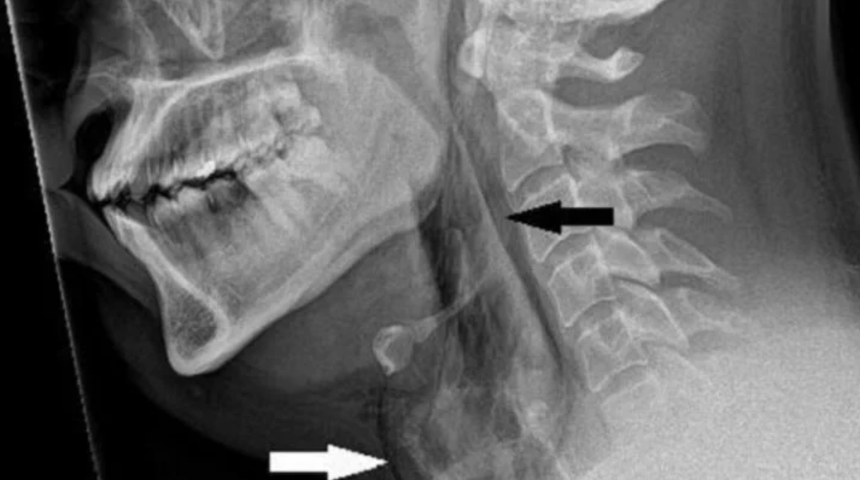

Şiddetli boyun ağrısı ve boynunun her iki yanında şişlik şikayetiyle acil servise başvuran şahsın, nefes alma, yutkunma ve konuşma ile ilgili herhangi bir sorununun olmadığı öğrenildi. Bilgisayarlı tomografi (BT) taramasında, hapşırık sırasında basıncın hızla artması nedeniyle nefes borusunda 2x2 milimetrelik bir yırtılma olduğu ortaya çıktı.

Doktorlar adamın ameliyata gerek duymadığı sonucuna vardı. Bunun yerine oksijen seviyelerinin ve diğer hayati belirtilerinin stabil kalmasını sağlamak için iki gün boyunca izlendi. Daha sonra ağrı kesici ve ateş düşürücü ilaçla hastaneden taburcu edildi. İki hafta boyunca yoğun fiziksel aktiviteden kaçınması önerildi. Sanook'un bildirdiğine göre, beş hafta sonraki bir takip raporu, CT taramasında da ortaya çıktığı gibi, yaranın iyileştiğini gösterdi.